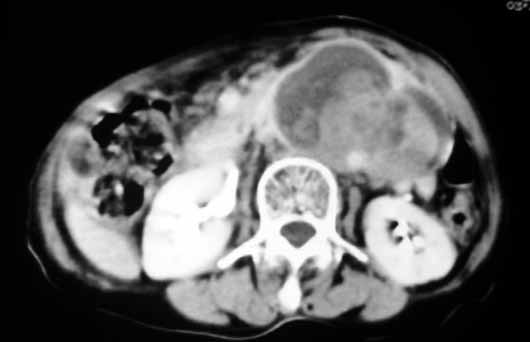

以下是引用天南地北在2007-4-30 17:42:00的发言:[br]增强扫描显示腹主动脉给包绕、推移。肿块不规则强化,[br]修正我在平扫的诊断[br]支持考虑:间叶源性肿瘤可能性大

以下是引用余辉在2007-4-30 18:01:00的发言:[br]病灶前方的条状增强影是什么?若是胰腺,位置似乎有点低,若是十二指肠,似乎又不诫该是那样强化,姑且将其看作胰腺吧,那么考虑来源于胰腺粘液囊腺瘤可能性大,其次考虑来源于肠系膜或者后腹膜的肿瘤如平滑肌肉瘤,异位嗜铬细胞瘤及淋巴瘤等。

以下是引用zyx168在2007-4-30 23:24:00的发言:[br]考虑:间叶源性肿瘤可能性大